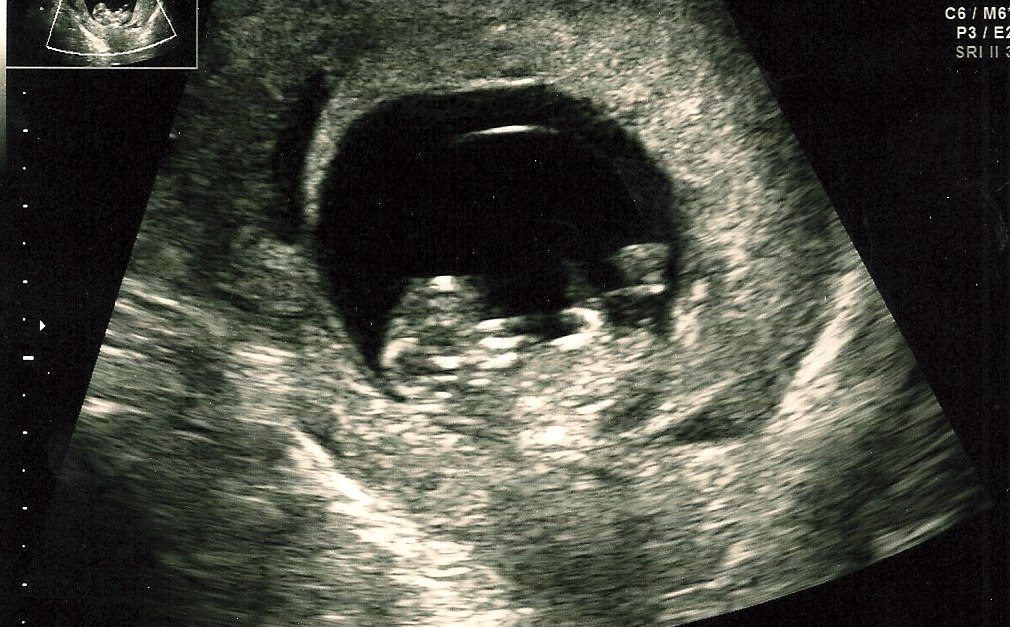

Jeg fik en tilbudt en pga rygmarvsbrok i min tidligere graviditet.. Fik den i uge 10.. Resultatet var det her..

Vedhæftede fotos (klik for at se i fuld størrelse)